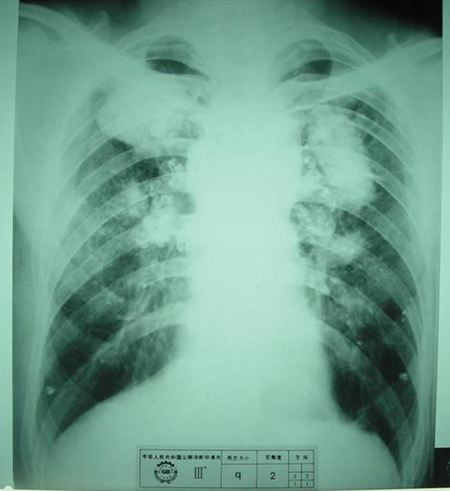

3)大阴影:在X射线胸片上,肺野内直径或宽度超过10mm的阴影,为晚期矽肺的重要X射线表现,形状有长条形、圆形、椭圆形、或不规则形,病理基础是团块状纤维化。大阴影的发展可由圆形小阴影增多、聚集,或不规则小阴影增粗、靠拢、重叠形成;多在两肺上区出现,逐渐融合成边缘较清楚、密度均匀一致的大阴影,常对称,形态多样,呈八字形等,也有先在一侧出现;大阴影周围一般有肺气肿带的X射线表现。

3)尘肺叁期:有下列表现之一者:

a) 有大阴影出现,其长径不小于20mm,短径不小于10mm;

b)有总体密集度为3级的小阴影,分布范围超过4个肺区并有小阴影聚集;

c) 有总体密集度为3级的小阴影,分布范围超过4个肺区并有大阴影。